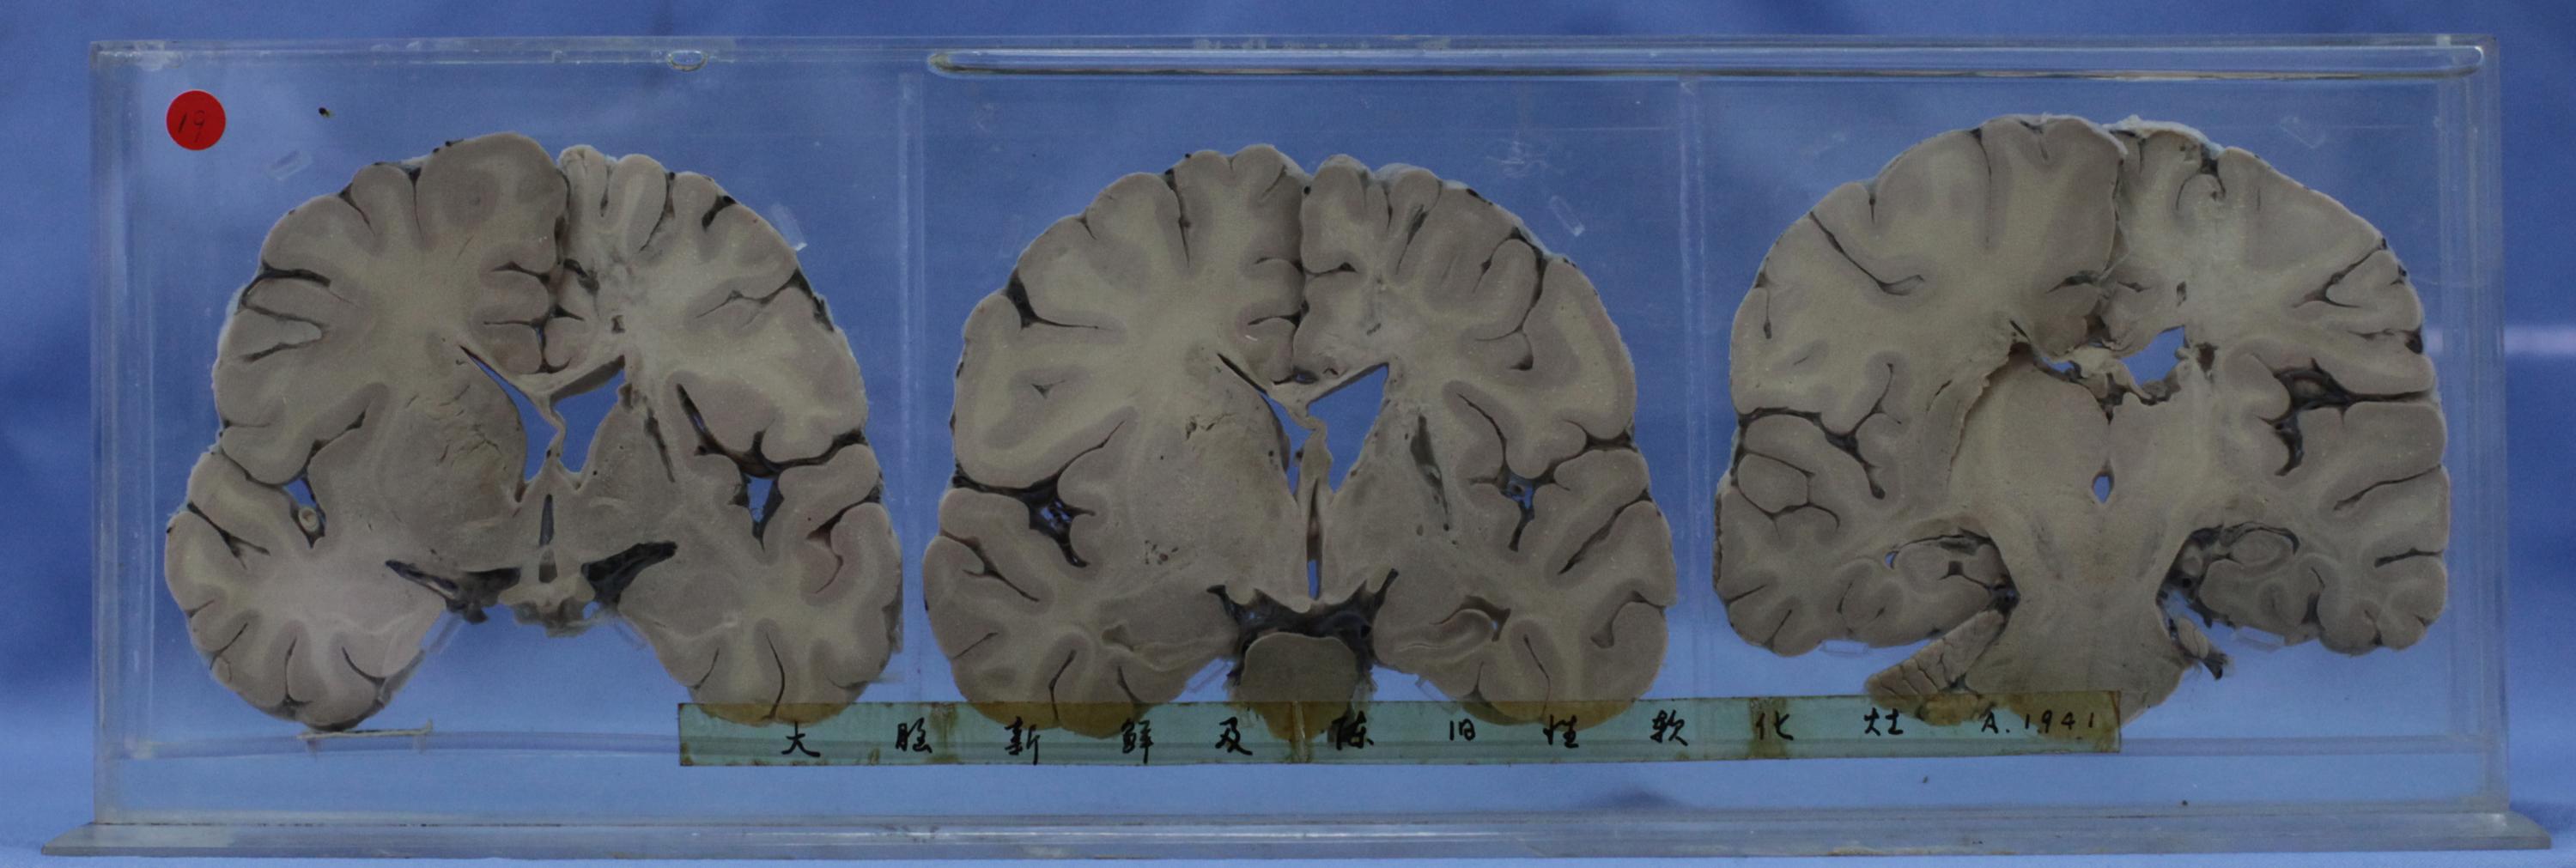

神经疾病-59-19. 大脑液化性坏死

大脑半球系列垂直切面分别经过前联合(左)、乳头体(中)、中脑(右),标本自左往右认定为脑片1(左)、脑片2、脑片3(右侧)。

脑片1大脑侧裂和脑底部血管断面见管壁增厚、血管硬化,右基底节最上方可见陈旧性腔梗,已液化;

脑片2(中间)双侧基底节可见散在小灶性梗死,部分组织腐脱;脑片3经中脑断面可见黑质,其侧脑室可见一液化坏死灶,0.2-0.5cm。